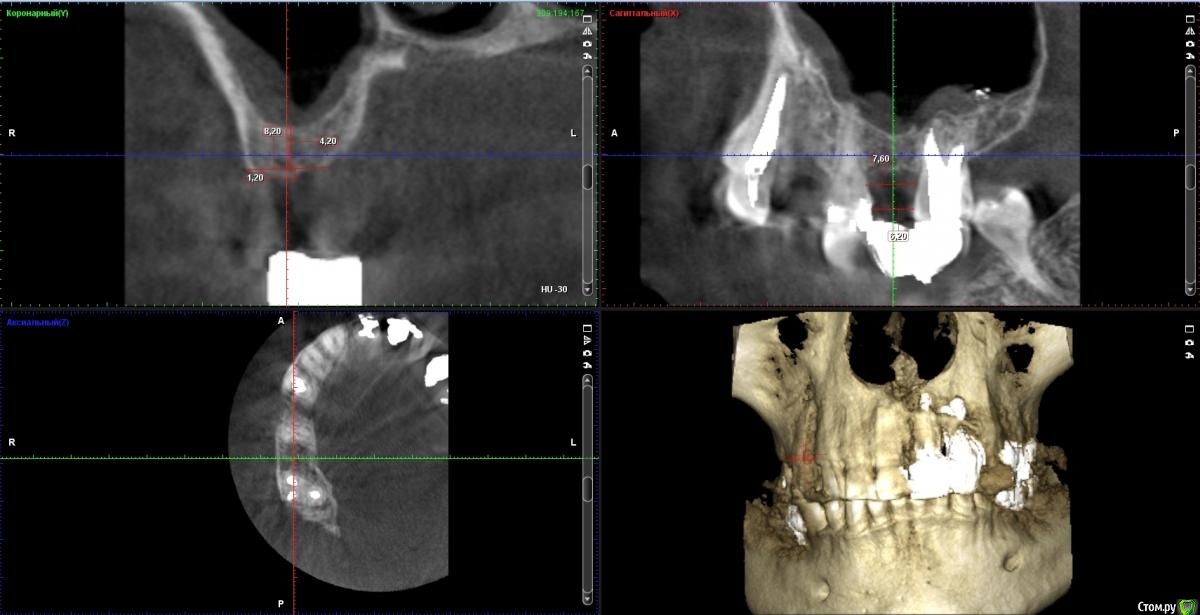

zumanok Опубликовано 21 декабря, 2020 Поделиться Опубликовано 21 декабря, 2020 Здравствуйте коллеги. Прошу Вашего мнения. Как Вы считаете можно ли обойтись в данном случае имплантатом Штрауман с широкой шейкой 4,8х8 + ЗСЛ остеотомами или делать ОСЛ и ставить любой имплантат? Ссылка на комментарий

Bier Опубликовано 22 декабря, 2020 Поделиться Опубликовано 22 декабря, 2020 4.8*6 ставьте. Тут при закрытом вы потеряете апикальную фиксацию и за счет развальцовывания корональной кости под гладкую шейку потеряете и корональную фиксацию.А 4.8*6 можно бикортикально поставить. 1 Ссылка на комментарий

stommm Опубликовано 23 декабря, 2020 Поделиться Опубликовано 23 декабря, 2020 Без орто или удаление 17 будет премоляр. 4.8 и тем более 6.5 (диаметр широкой шейки штр) слишком широкие. Я бы брал 4.1х8 блт. Может 4.1х8 с шейкой. Но не wn точно. Все имхо конечно. 2 Ссылка на комментарий

zumanok Опубликовано 23 декабря, 2020 Автор Поделиться Опубликовано 23 декабря, 2020 Коллеги, большое спасибо за ответы. Думал взять штрауман ради шейки и возможности сильно не заглублять. Только сейчас понял что можно обойтись практически любым имплантатом + сст т.к. между зубами действительно не получается полноценного моляра и будет возможность размоделировать нормально. 17.Зуб пациент отказался удалять. Ссылка на комментарий